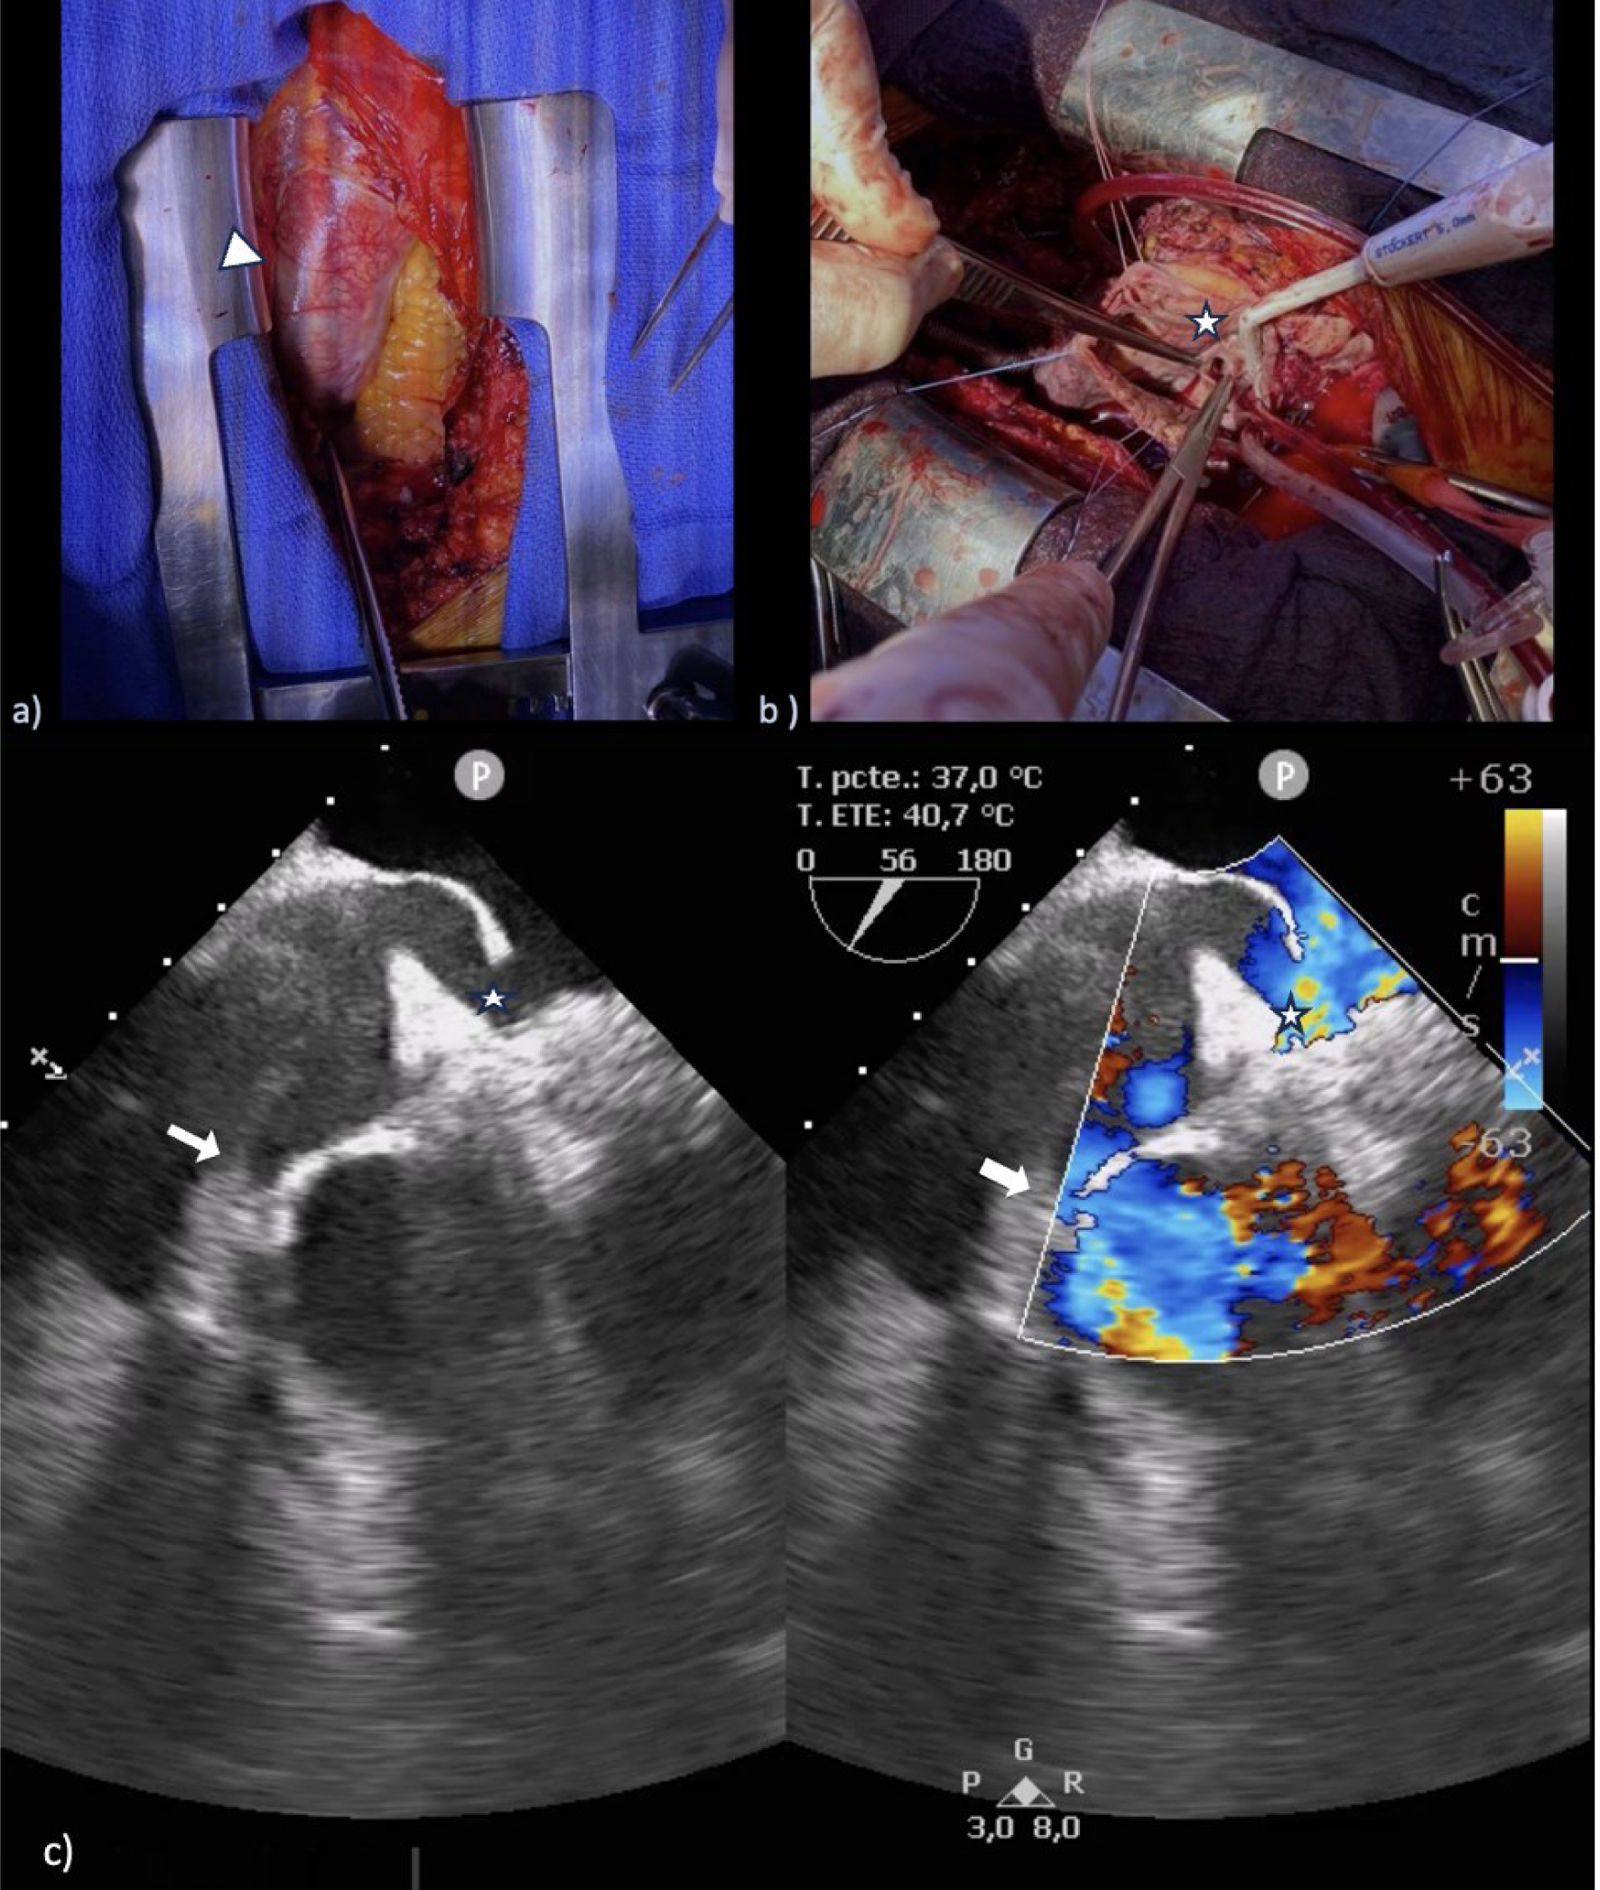

Platypnea-orthodeoxia syndrome from aortic distortion

Síndrome de platipnea-ortodeoxia por distorsión aórtica

Department of Cardiovascular Surgery, Complexo Hospitalario Universitario A Coruña (CHUAC), A Coruña, Spain